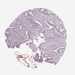

CANCER COLORECTAL CANCER Show tissue menu

Colorectal cancer

Human cancer

Colon adenocarcinoma